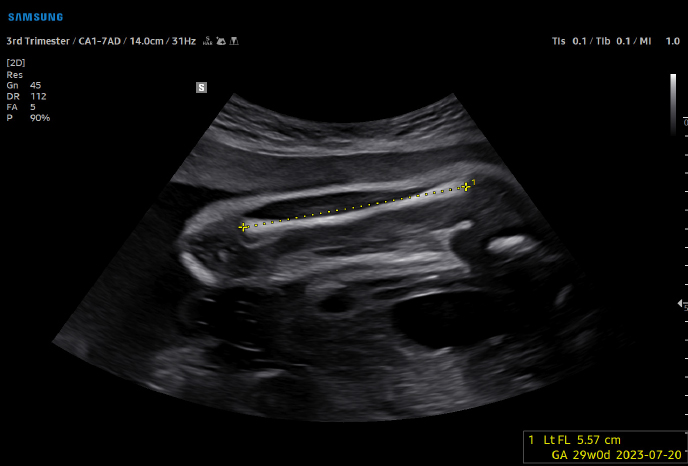

하이앤드 초음파 장비를

활용한 정밀 심장 검사

심장 질환 진단에서 가장 중요한 것은 ‘심장의 상태를 얼마나 정확하게 볼 수 있느냐’입니다. 저희 센터는 대학병원급 하이앤드 초음파 장비를 도입하여, 실시간 3D 렌더링으로 정밀 진단이 가능하며, 심장의 구조·혈류·기능을 실시간 고해상도로 관찰합니다.

미세한 판막 움직임, 혈류 속도 변화, 심방·심실 크기와 수축력까지 정밀하게 분석할 수 있어, 심장질환의 조기 발견과 치료 계획 수립에 큰 차이를 만듭니다.